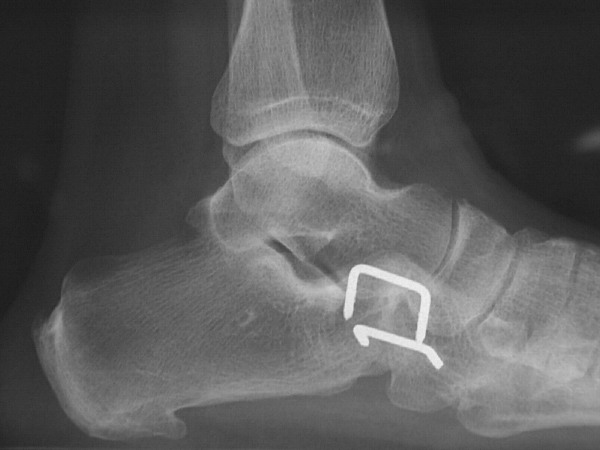

What if patients do require surgery? True cuboid syndrome surgical therapy deals with stabilization of the joint. Three options exist for cuboid stabilization. The treatment options depend on the patient and how willing he or she is to consider further surgery if more conservative surgical cases do not work. The first surgical procedure choice is an arthroscopy of the cuboid-calcaneus joint with a capsular shrinkage of the plantar ligaments. One would do this with an arthroscopic shrinkage device usually used in shoulder stabilization. The procedure takes some time to learn but is fairly simple to perform. Two months of stabilization with casting and nonweightbearing is necessary to allow for added stabilization. The second type of surgical option is a fresh frozen cadaveric tendon stabilization of the calcaneocuboid joint. One would essentially do this through a weave type procedure in which one weaves a tendon about the lateral joint so it can act as a ligamentous stabilizer of the joint. The final and most definitive procedure is a fusion of the calcaneocuboid joint. The procedure is not very difficult to perform and does not cause much stiffness or loss of function of the foot or ankle. It is essential to perform rigid internal or external fusion as the rate of non-union is high in this joint when compared to other rearfoot fusions due to the increased motion associated with this joint. What about the fourth and fifth metatarsocuboid joint? Be very cautious fusing these joints as the rate of non-union is high. Also be aware that these patients sometimes have postoperative pain due to the increased demand for motion at these joints. If there is severe degeneration of these joints, it may be better to perform an arthroplasty of the joints instead of a fusion.